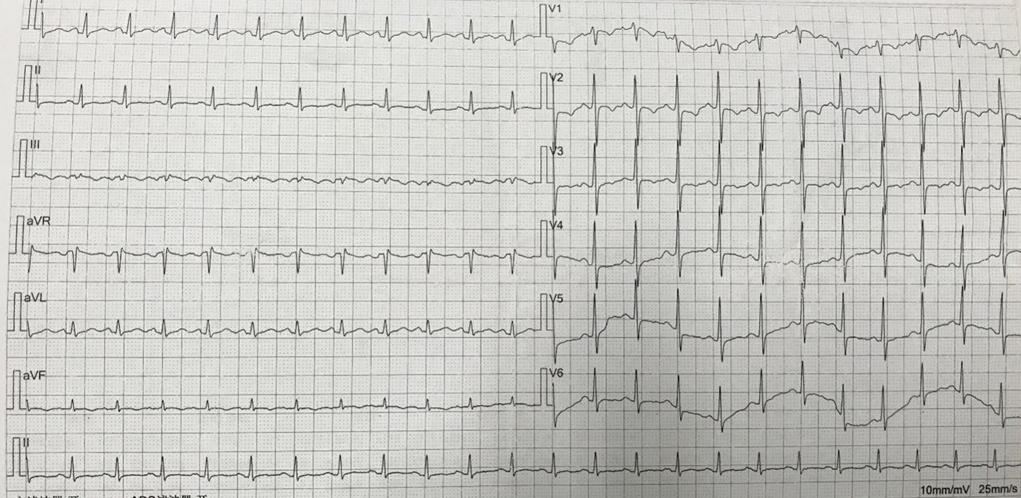

▎ 心电图:窦性心动过速,胸前导联T波低平,倒置。

图1:患者入院心电图